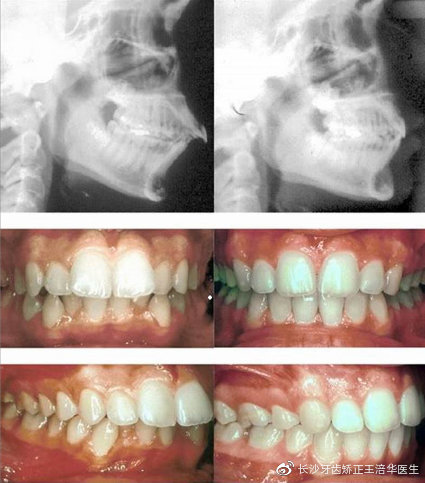

下巴后缩通常是骨性的,如果是在生长发育期的儿童与青少年, 可以通过SGTB矫治器,控制上颌发育,下巴导出的效果、

在后牙矫治器上形成颌垫,通过上下颌颌垫之间的斜面将下颌前导到前伸的位置,通过逐步建立后牙咬合,从而使颌位稳定来达到正确的咬合关系。随后,慢慢降低颌垫的高度,直到咬合完全稳定。这时候,颌位已经回到了它本该在的位置,下巴也出来了。

上述矫正手段对于处在青春期的青少年来说,是很明显的,对于成年人来说,更多是通过正畸牙齿来改善下巴后缩的问题。从而让原本很糟糕的面部比例,看上去更加自然。

如果成年患者骨性下巴后缩较为严重,通过牙齿整牙对下巴改善效果不明显,理想的治疗方法是正畸+正颌联合治疗。